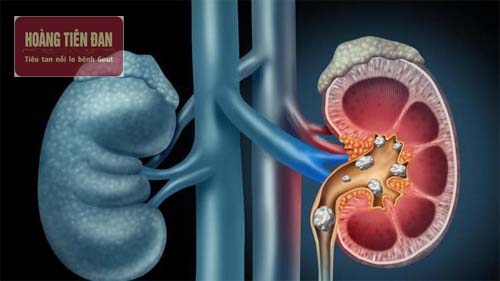

Sỏi thận được đánh giá là một trong các bệnh lý ở đường tiết niệu vô cùng nguy hiểm. Khi các viên sỏi lớn dần và gia tăng kích thước, chúng có thể làm tắc nghẽn đường tiểu, gây đau đớn dữ dội. Nghiêm trọng hơn, nó có thể gây ra viêm bể thận cấp và mạn tính, làm nhiễm trùng đường tiết niệu, gây suy thận cấp tính và mạn tính, ứ mủ bể thận, vỡ thận, đe dọa đến tính mạng của người bệnh, thậm chí gây tử vong. Vì thế cần phải chẩn đoán bệnh sớm và điều trị kịp thời để tránh xảy ra hậu quả nghiêm trọng.

Theo các chuyên gia y tế không phải trường hợp nào bị sỏi thận cũng đều có triệu chứng. Các số liệu thống kê cũng cho thấy có đến gần một nửa số bệnh nhân bị sỏi thận đều không có triệu chứng nên rất khó có thể chẩn đoán bằng mắt thường. Cách tốt nhất là phải đến các cơ sở y tế để có các biện pháp chẩn đoán hình ảnh chính xác nhất.